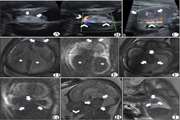

Ultrasound and magnetic resonance imaging features of fetal urogenital anomalies: A pictorial essay Jul 15 2025 - 10:59

Effect of Oligopin Administration on Ovarian Morphology in Women with Polycystic Ovarian Syndrome (PCOS) Jul 15 2025 - 09:58